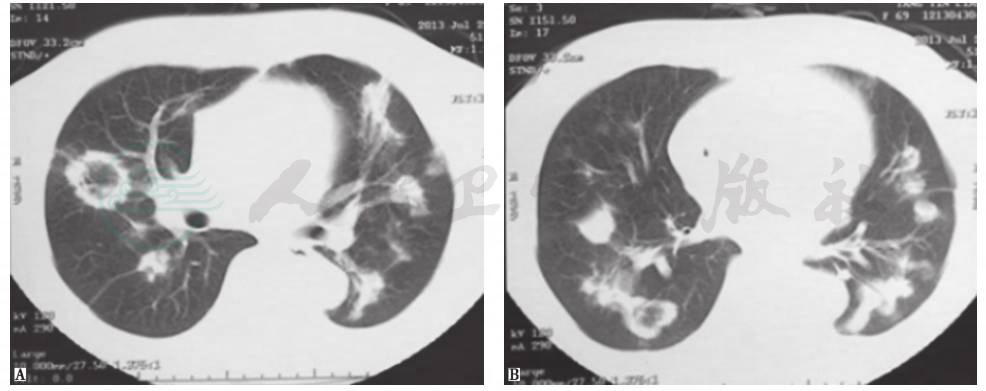

患者经口服糖皮质激素抗炎治疗后稳定恢复,复查胸部CT见图10~图12。

图10 治疗8天时胸部CT表现

胸部CT见双肺原有病灶明显吸收,胸腔积液消失

图11 治疗22天时胸部CT表现

胸部CT见双肺原有病灶明显吸收,部分病灶完全吸收

图12 治疗3个月时胸部CT表现

胸部CT见双肺原有病灶完全吸收消失